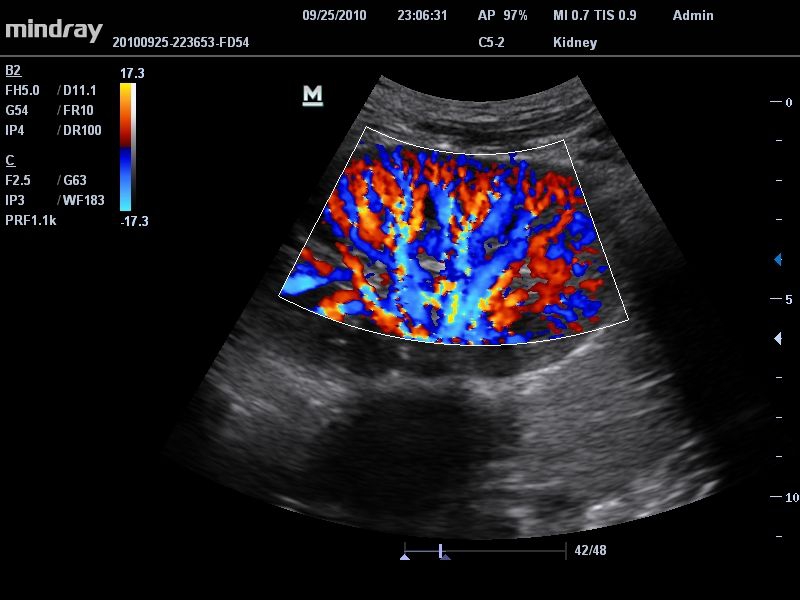

УЗИ-аппарат

Mindray DC-T6

Ультразвуковая система Mindray DC-T6 – это инновационный аппарат для проведения высокого уровня диагностики с качественной визуализацией и широким спектром применения. Платформа рекомендована для использования в коммерчески многопрофильных медицинских учреждениях и государственных лечебных клиниках.

Цветовой допплер:

Да

• Режимы сканирования: B/M/CFM/PDI/Направленный PDI/PW, HPRF, Тканевая гармоника, М- и цветной М-режим.